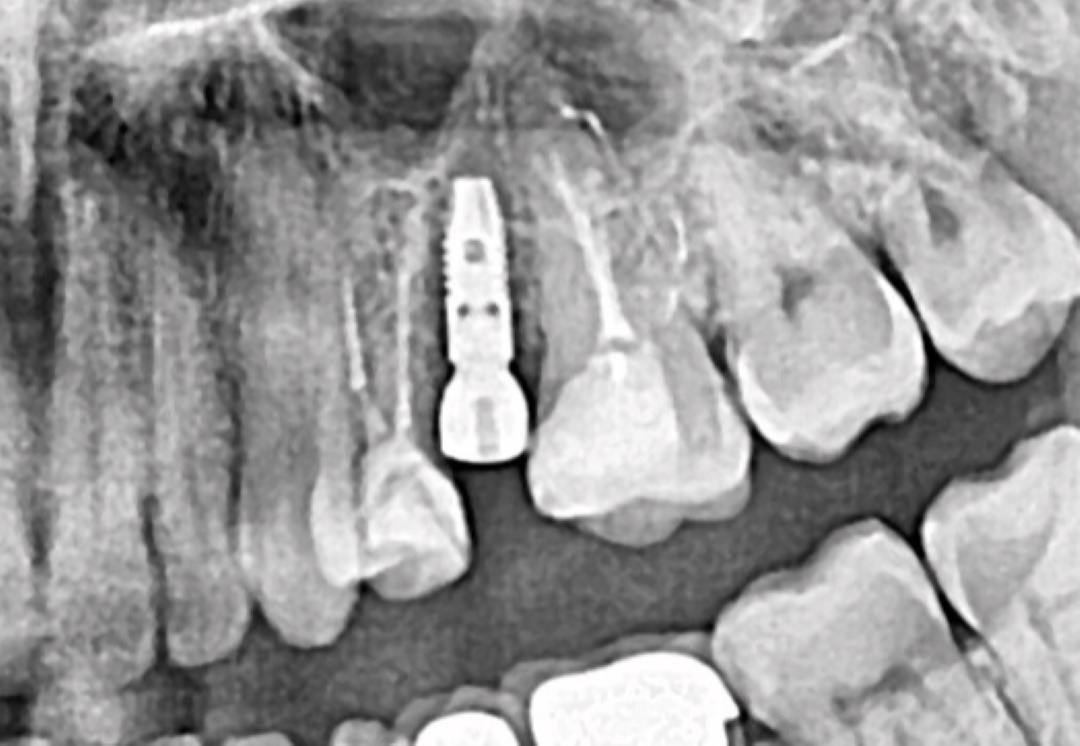

Наша цель:

Зуб 11 ранее депульпированый, восстановленный циркониевой реставрацией (как и все остальные зубы). По данным клкт мы видим небольшой очаг деструкции костной ткани и предполагаем трещину корня. Также имеется увеличенный люфт зуба в передне-заднем векторе и незначительный дискомфорт...

Наша задача:

Максимально атравматично удалить зуб 11, установить имплантат с уверенным торком и провести временное протезирование. Пациент должен уйти с зубом.

Пару слов о Сложности...

Чисто технически - для меня на день сегодняшний данные операции полностью отработанный протокол - но все равно остаются небольшие риски потерпеть неудачу или одержать неполную победу (что для меня равносильно неудаче) и об этом я всегда помню.

Чисто психихологически - очень тяжело - пациент доверяет, верит в меня и товарища Михаила Нагрелли /@dr.m.nagrelli/, зона отвественности огромна, как и возложенные на нас ожидания, а еще и фронтальный отдел, а еще и приезжий пациент, а еще и врач...

Путь у успеху:

- Максимальная аккуратность и филигранность во всем. Разрезы, удаление, подготовка ложа, швы. Фронтальный отдел не дает возможности переиграть, сменить позицию, пересверлиться и тд...

- Четкий план - размеры импланта, позиция, временный абатмент...

- Немедленная нагрузка...

- Незаметность - зашли и вышли - как будто нас там не было!

Дальше все сами увидите...

PS...

Имплант: наш выбор очевиден на сегодня это - Straumann BLT 3.3*10mm SLActive!

Закрытие костного дефекта: Auto + Straumann Xenograft!

Временный абатмент: оригинал Straumann /потому что имеет золотисто-желтый цвет/...

Операция с применением навигационной хирургии!

P.S. Верхняя челюсть тоже требует оперативных вмешательств. Сейчас мы определяем план лечения и варианты протезирования верхней челюсти. Думаю скоро будет пост с продолжением этого случая.